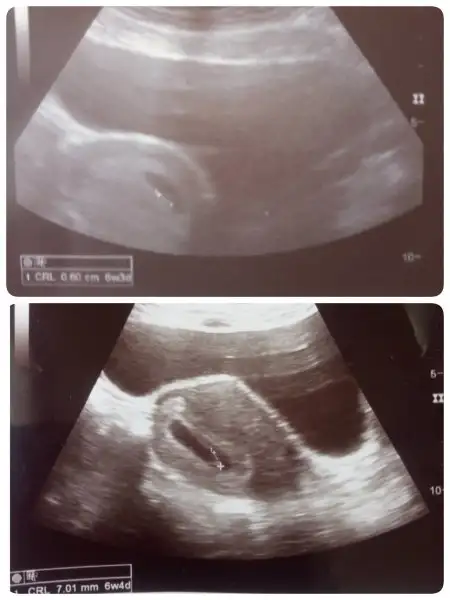

340 2 gün sonra birden 1500 e çıktı ve kese göründü 1 hafta sonra da bebiş ve kalp atışı...sat a göre 1 hafta gerideyiz dr geç yumurtlamışsındır dedi...keşke düzenli baktırsaydın beta hcg ne en azından az da olsa yükselme olup olmadığı anlaşılırdı...benim bu düzensiz beta ya bile dr lar kötü dememişti % 66 yükselmesi yeterli demişlerdi inşallah hakkında hayırlısı olur...

inşallah hakkında hayırlısı olsun...340 çıktığı gün 1 damla kadar kanama oldu peçeteye ben düşecek diye düşünürken 2 gün sonra 1500 oldu değer ve 2,2 mm lik minicik bir kese göründü o kanama yerleşme kanamasıymış demekki diye düşündüm ve birden 1500 e çıkması da bunun kanıtı gibiydi...ilk hafta böyle dalgalanma olabiliyormuş ve her düzensiz artış sağlıksız gebeliğe işaret değilmiş gönlünü ferah tut Allah a sığın bol bol dua et canım...Kardelen bana umut oldun inşallah ya.. İnşallah Çarşamba tekrar bakılacak